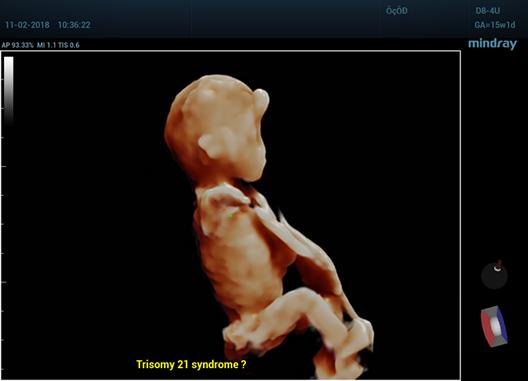

Care este diferenta dintre ecografia 2D, 3D si 4D?

Foto 1/7